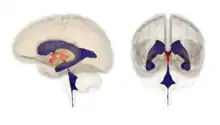

Alongside the absence of pleasure, other noticeable changes include psychomotor retardation, disrupted patterns of sleeping and feeding, a loss of sex drive and motivation—which are all also characteristics of the body's reaction to actual physical pain. In depressed people there is an increased activity in the regions of the cortex involved with the perception of pain, such as the anterior cingulate cortex and the left prefrontal cortex. This activity allows the cortex to manifest an abstract negative thought as a true physical stressor to the rest of the brain.[14][15][16][17][18][19][20][21][22][23]

One way depression increases the individual's focus on a problem is by inducing rumination. Depression activates the left ventrolateral prefrontal cortex, which increases attention control and maintains problem-related information in an "active, accessible state" referred to as "working memory", or WM. As a result, depressed individuals have been shown to ruminate, reflecting on the reasons for their current problems. Feelings of regret associated with depression also cause individuals to reflect and analyze past events in order to determine why they happened and how they could have been prevented.[26] The rumination hypothesis has come under criticism. Evolutionary fitness is increased by ruminating before rather than after bad outcomes. A situation that resulted in a child being in danger but unharmed should lead the parent to ruminate on how to avoid the dangerous situation in the future. Waiting until the child dies and then ruminating in a state of depression is too late.[27]

The third ventricle hypothesis of depression proposes that the behavioural cluster associated with depression (hunched posture, avoidance of eye contact, reduced appetites for food and sex plus social withdrawal and sleep disturbance) serves to reduce an individual's attack-provoking stimuli within the context of a chronically hostile social environment.[42][43][44] It further proposes that this response is mediated by the acute release of an unknown inflammatory agent (probably cytokine) into the third ventricular space. In support of this suggestion, imaging studies reveal that the third ventricle is enlarged in depressives.[45][46]